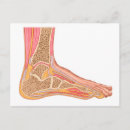

Section Longitudinale Du Pied Humain

Prix de vente 6,48 $CA. Prix Initial 7,20 $CA.